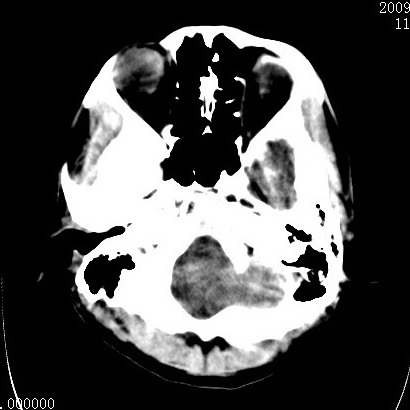

以下是引用余辉在2009-4-9 17:34:00的发言:[br]双侧脑白质对称性弥漫性密度减低,脑室脑沟裂池变小,双侧豆状核对称低密度,脑干对称性低密度,考虑1中毒性脑病2电解质异常(低钾钠等)3代谢异常及维缺乏等,进一步检查。